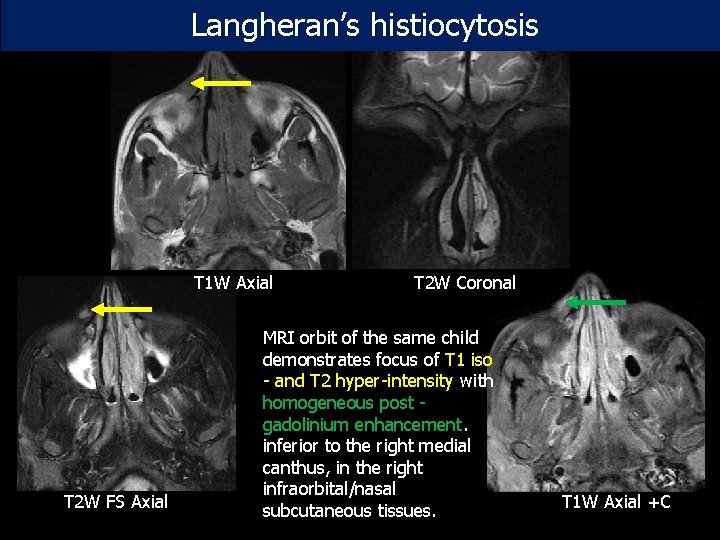

Langheran’s histiocytosis T 1 W Axial T 2 W FS Axial T 2 W Coronal MRI orbit of the same child demonstrates focus of T 1 iso - and T 2 hyper-intensity with homogeneous post - gadolinium enhancement. inferior to the right medial canthus, in the right infraorbital/nasal subcutaneous tissues. T 1 W Axial +C